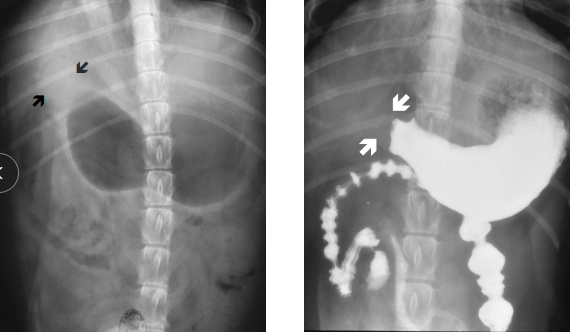

Gastric Dilatation-Volvulus (GDV)

Et: Rapid distention of stomach with air + volvulus @ axis

Compression of caudal vena cava → ↓ venous return → hypovolemic shock

EMERGENCY

Sig: Old, Lg, deep chest, rapid eating, aerophagia, raised food bowls, anxiety

Cs: non-productive retching, salivation, distention, tympany, tachycardia, weak pulse, shock

Dt: R-Lateral abdominal rads, double bubble, ↑ PCV, metabolic acidosis, coagulation defects

Tx:

Initial: LRS shock fluids, O2, Gastric decompression (NG tube or trocarization), Antibiotics

Sx: Emerg Gastropexy

Prevent: Prophylactic gastropexy, slow feeding, sm meals

Food Bloat

Et: over - eating

Cs: acute distention, panting, drooling, retching

Dt: r/o GDV →R-Lateral abdominal rads w/ uniform food-filled stomach

No volvulus present, rule out GDV

Tx: fluids, analgesics, gastric lavage

Supportive

resolves < 24-48hr, good Px